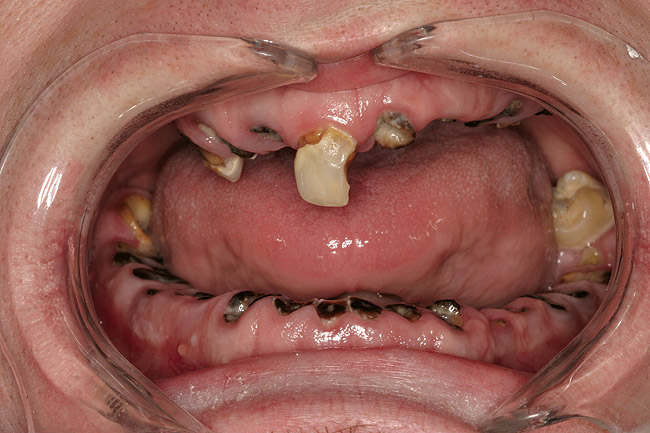

Joe soon learned how to manufacture the drug. His need for meth soon consumed his every thought. He basically lived to do more meth. He admitted that he had made some poor choices. Unfortunately once the addiction kicked in, he no longer had a choice, he had to use. This was his end result (Figure 4 through Figure 6). From these photographs, one might think that he had used the drugs his entire life; however, this progression happened over the course of only about 1 year of smoking the drug. Because of the caustic chemicals (muriatic acid, hydrochloric acid, lithium, etc) his teeth started to blacken, then break.

Figure 4  PRESENTATION CONDITION By the time Joe presented for treatment after serving time in prison and going to rehab, his teeth were completely destroyed by rampant decay. Although some teeth could have been saved, the patient chose to have all of the remaining teeth extracted in order to receive a set of full dentures.

Figure 4

Figure 5  PRESENTATION CONDITION By the time Joe presented for treatment after serving time in prison and going to rehab, his teeth were completely destroyed by rampant decay. Although some teeth could have been saved, the patient chose to have all of the remaining teeth extracted in order to receive a set of full dentures.

Figure 5

Figure 6  PRESENTATION CONDITION By the time Joe presented for treatment after serving time in prison and going to rehab, his teeth were completely destroyed by rampant decay. Although some teeth could have been saved, the patient chose to have all of the remaining teeth extracted in order to receive a set of full dentures.

Figure 6